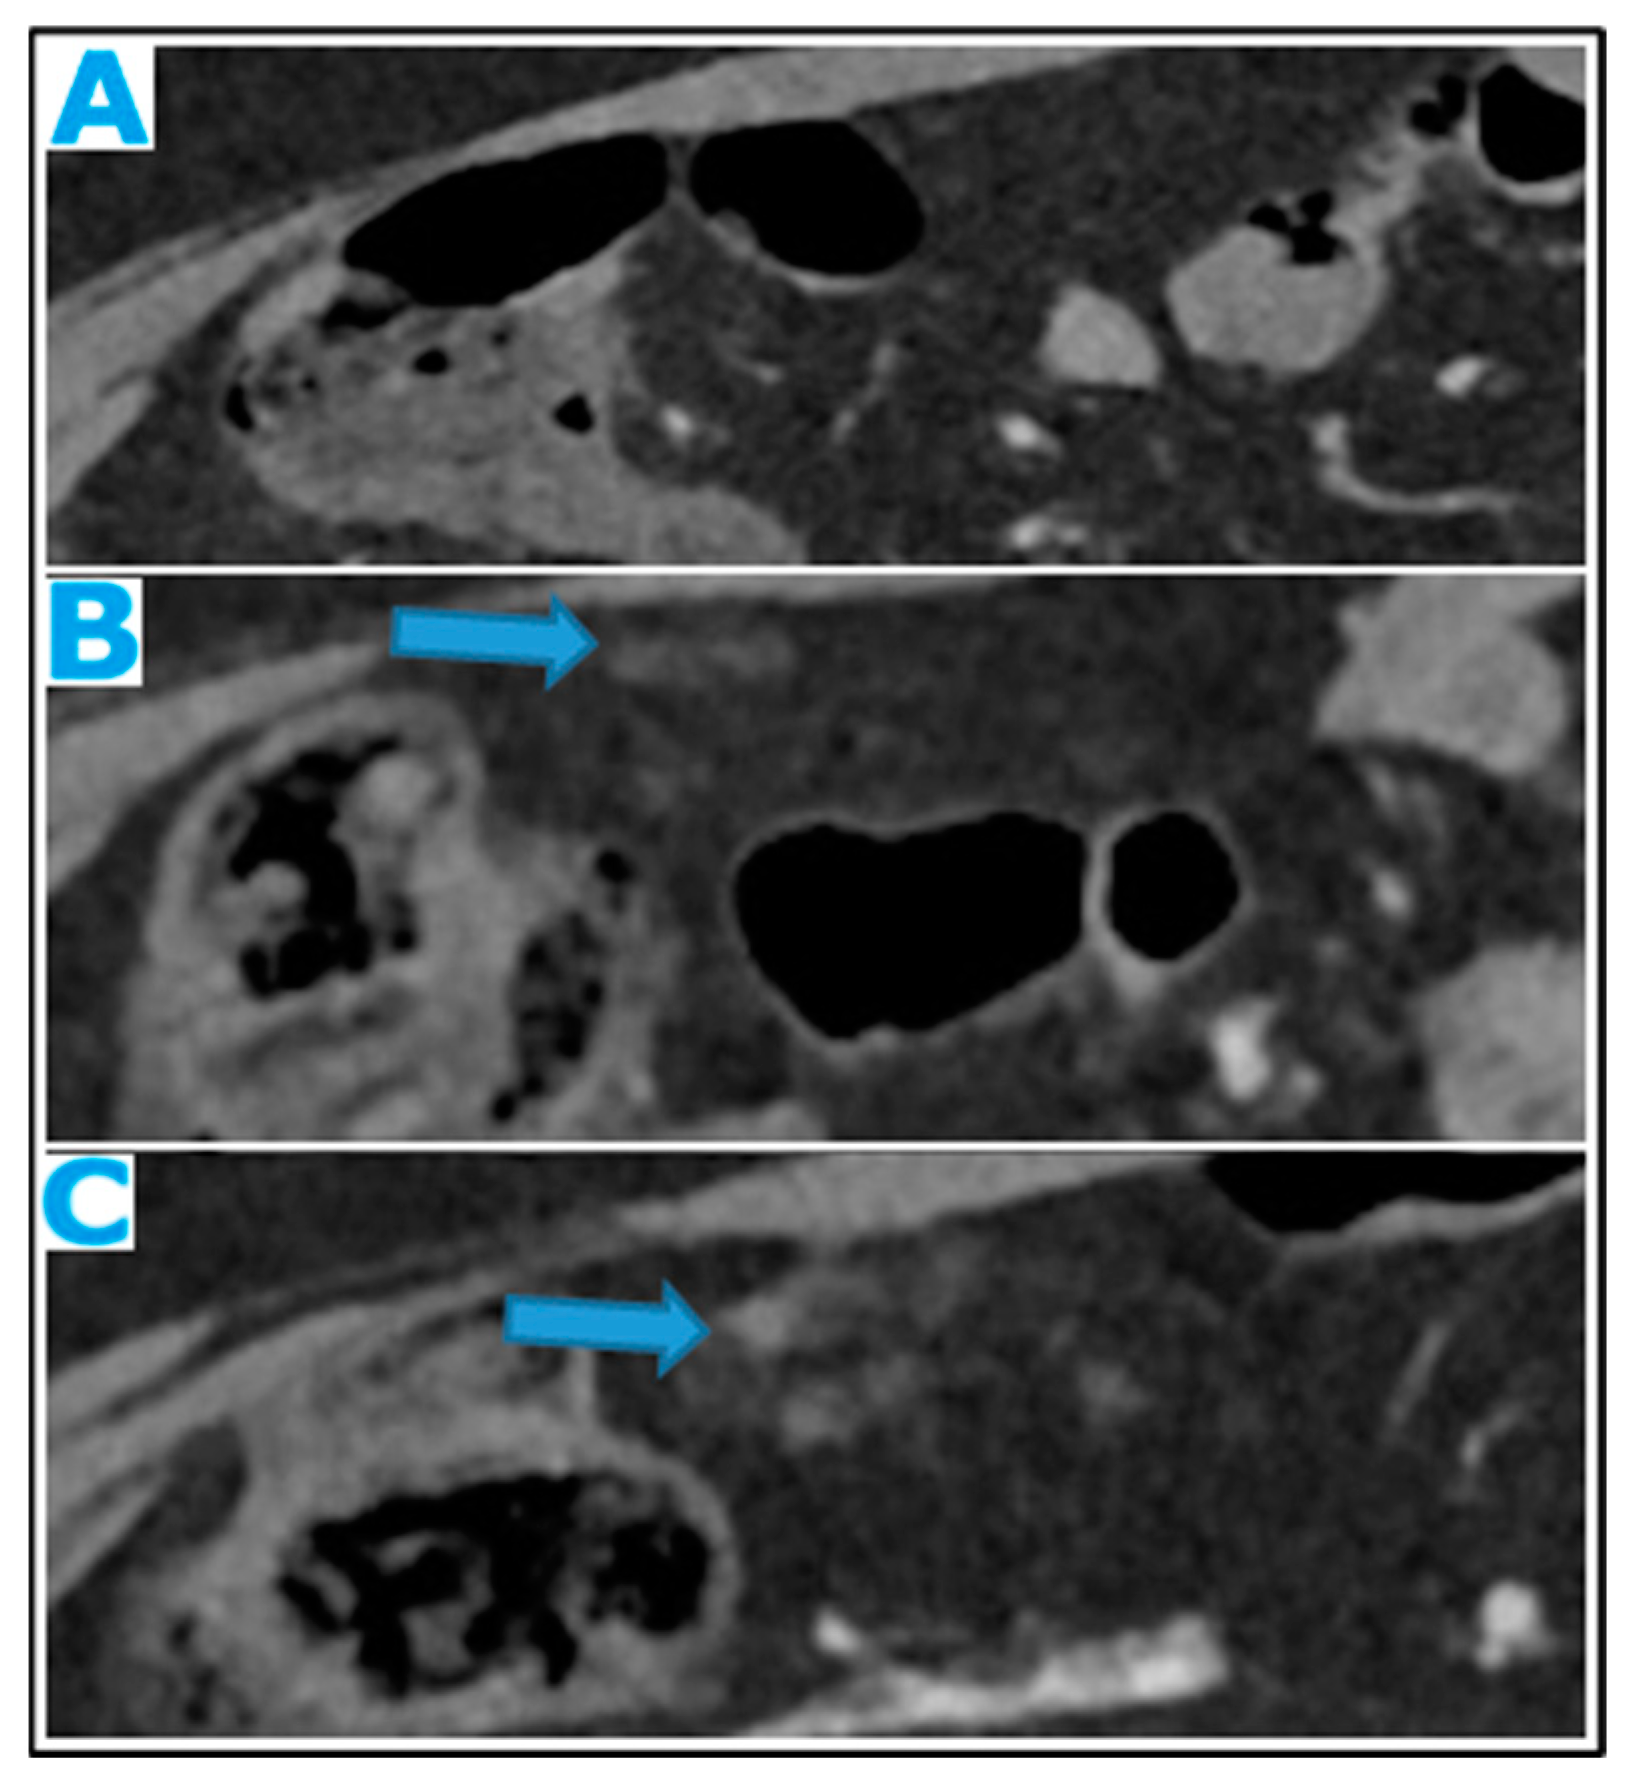

Figure 17.

Axial CE-CT (A): from one year prior (disease-free peritoneum), B from four months prior, C current follow up. Note the early stages and evolution of omental deposits (arrows).